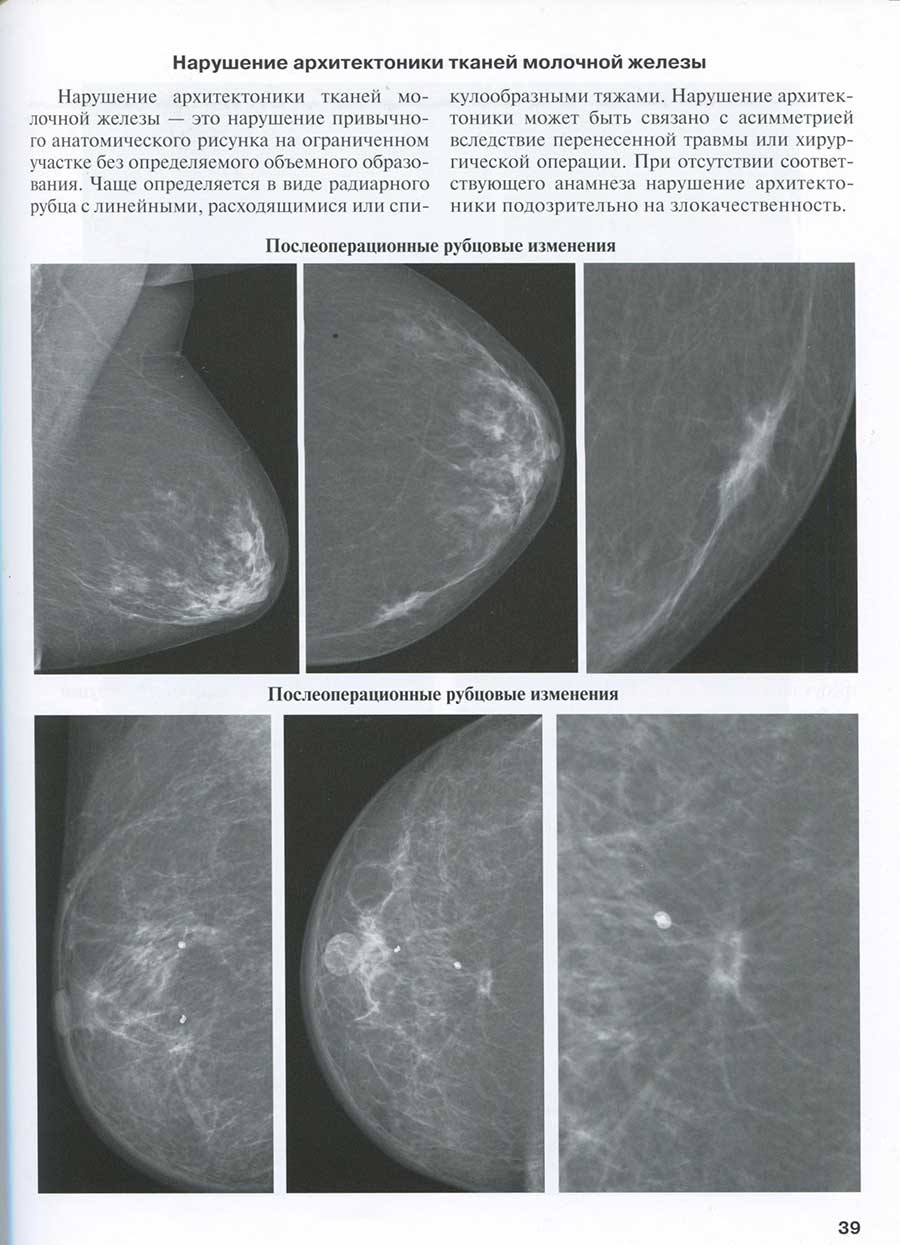

Нарушение архитектоники тканей молочной железы